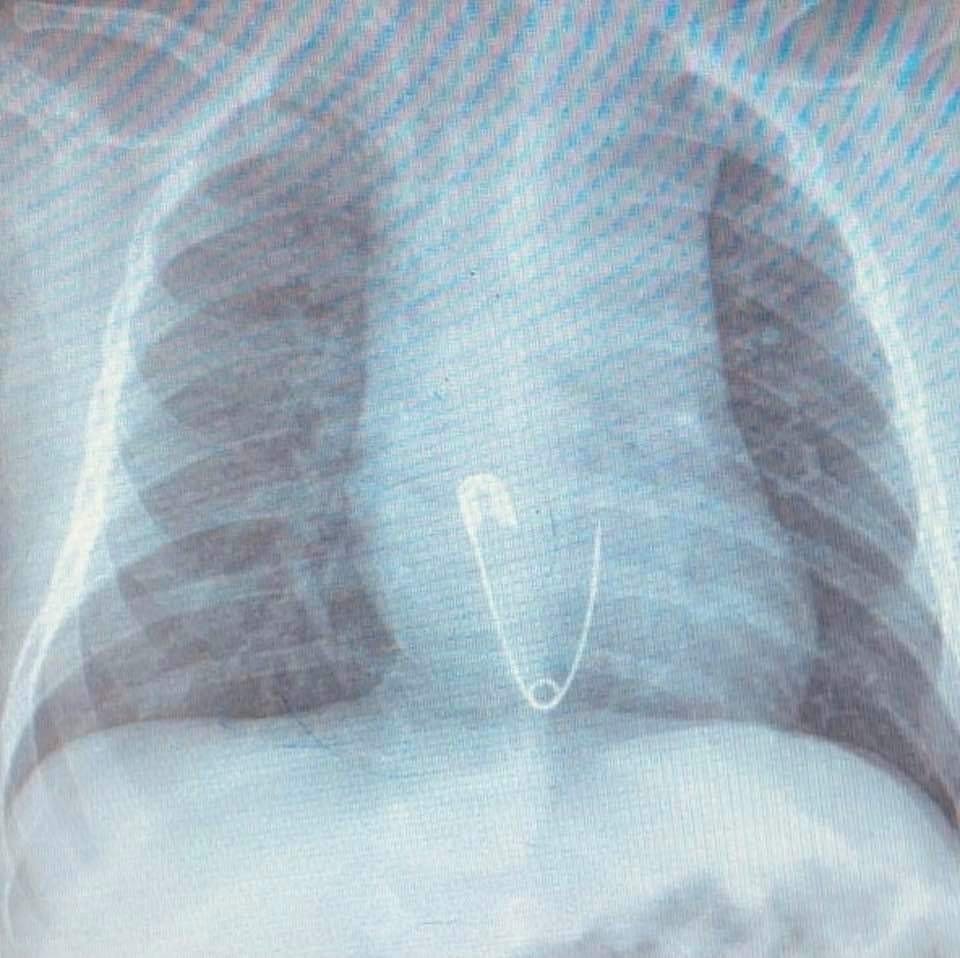

Hastanın Diyarbakır'dan Elazığ'a geldiğini belirten Prof. Dr. Yaşar Doğan, "Hastayı kabul ettik, 5 aylık bir hasta. Bize gelmeden önce üzerinde bulunan nazar boncuğunu çengelli iğne ile birlikte ağzına götürmüş. Aile de fark edince müdahale etmiş, ağzındaki nazar boncuğunu çıkarmış fakat o esnada çengelli iğne yemek borusuna kaçmış. Hasta geldiği zaman çektiğimiz röntgende çengelli iğne yemek borusunun alt kısmında takılı vaziyetteydi. Hastaya 15 dakikalık sedasyon altında işlem yapıldı, endoskopi ile parça çıkarıldı. Hasta şu anda gayet iyi. Biraz sonra da evlerine göndereceğiz" dedi.